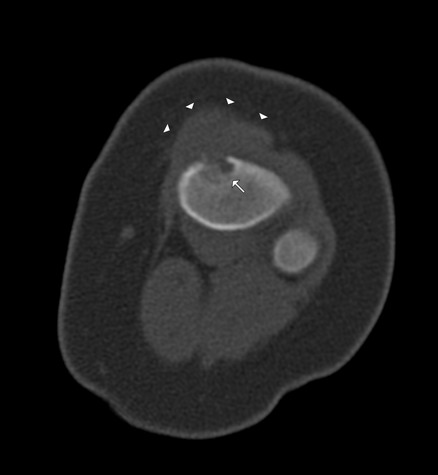

Figure 2: Axial CT image through the proximal tibia

demonstrates anterior lytic lesion with minor intramedullary

extension (white arrow) with significant pretibial soft tissue

component (white arrowheads).

1). CT imaging demonstrated a 5mm eccentrically located lucent

lesion in the proximal tibial metaphysis with cortical

destruction and a soft tissue mass (figure 2). MR imaging